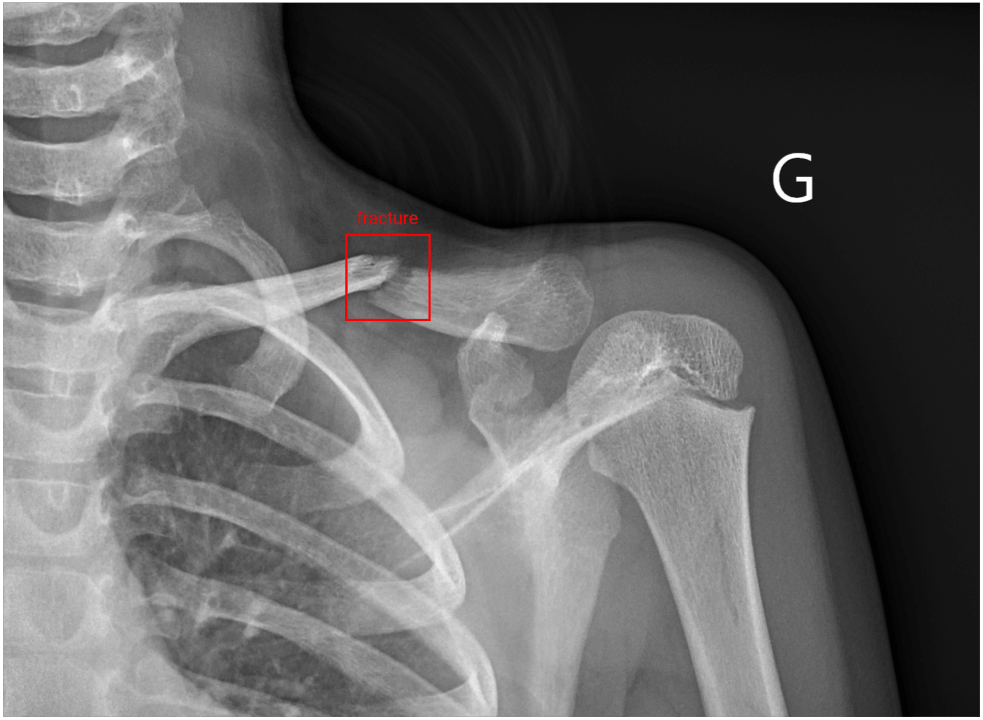

Example of an annotated image (label) Example of an annotated image (with label)

In radiology, we face this problem when we use our algorithms in medical centers different from those on which the training was performed. Over the past two years, we have developed at AZmed a high-performing detection system capable of automatically locating bone fractures on standard radiographs. We started with a state-of-the-art algorithm that excelled at object detection on natural images (i.e., everyday images), and we transformed it to excel at fracture detection on radiographic images.

Our ambition has always been to develop a model that generalizes across all centers. We therefore encountered domain adaptation challenges very early on. This is a real challenge, as we will see later, because each medical center is unique and has its own specificities. Beyond being an exciting challenge for AZmed’s researchers, solving this issue is essential for several reasons. Naively, to get around this problem, one might consider developing a custom algorithm for each medical center using only their own images for training. However, algorithms require thousands of images to achieve the desired performance. This idea would involve a heavy data collection task, followed by an annotation phase involving thousands of images. Indeed, the images provided to the algorithm must be manually labeled beforehand to enable learning. This is a time-consuming task that requires the expertise of several radiologists. Each image in our training dataset must go through the hands of three radiologists: the first writes a medical report, the second annotates the radiograph by drawing a box around the fracture, and the third validates or rejects the annotation.